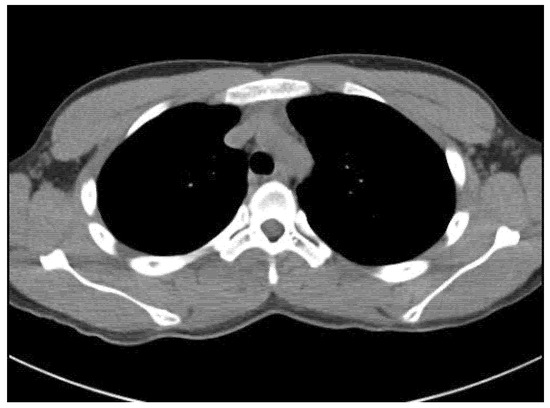

An 18-year-old male student came to our spine center complaining of aggravating right back pain that had started 5 months ago, along with swelling of the mid-thoracic level. At a local hospital, he underwent a chest and heart computed tomography exam for the evaluation of chest and back pain, but there were no abnormal findings on the images (Figure 1). The physician did extracorporeal shock wave therapy at his trunk for the treatment of vague pain about 6 weeks before visiting our institution. He explained that after the extracorporeal shock wave therapy, the back pain worsened, and swelling at the site of pain was found.

Figure 1. Chest CT taken at an outside hospital about 5 months prior to presentation demonstrates no abnormal mass lesion at the paraspinal area of the thoracic spine.